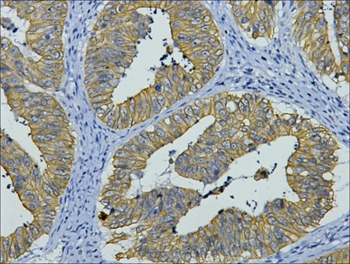

IHC staining of human colon cancer tissue with CK8 mouse mAb(8G8) diluted at 1:200.

Cytokeratin 8 belongs to the type B (basic) subfamily of high molecular weight keratins and exists in combination with cytokeratin 18. Cytokeratin 8 is primarily found in the non squamous epithelia and is present in majority of adenocarcinomas and ductal carcinomas. It is absent in squamous cell carcinomas.